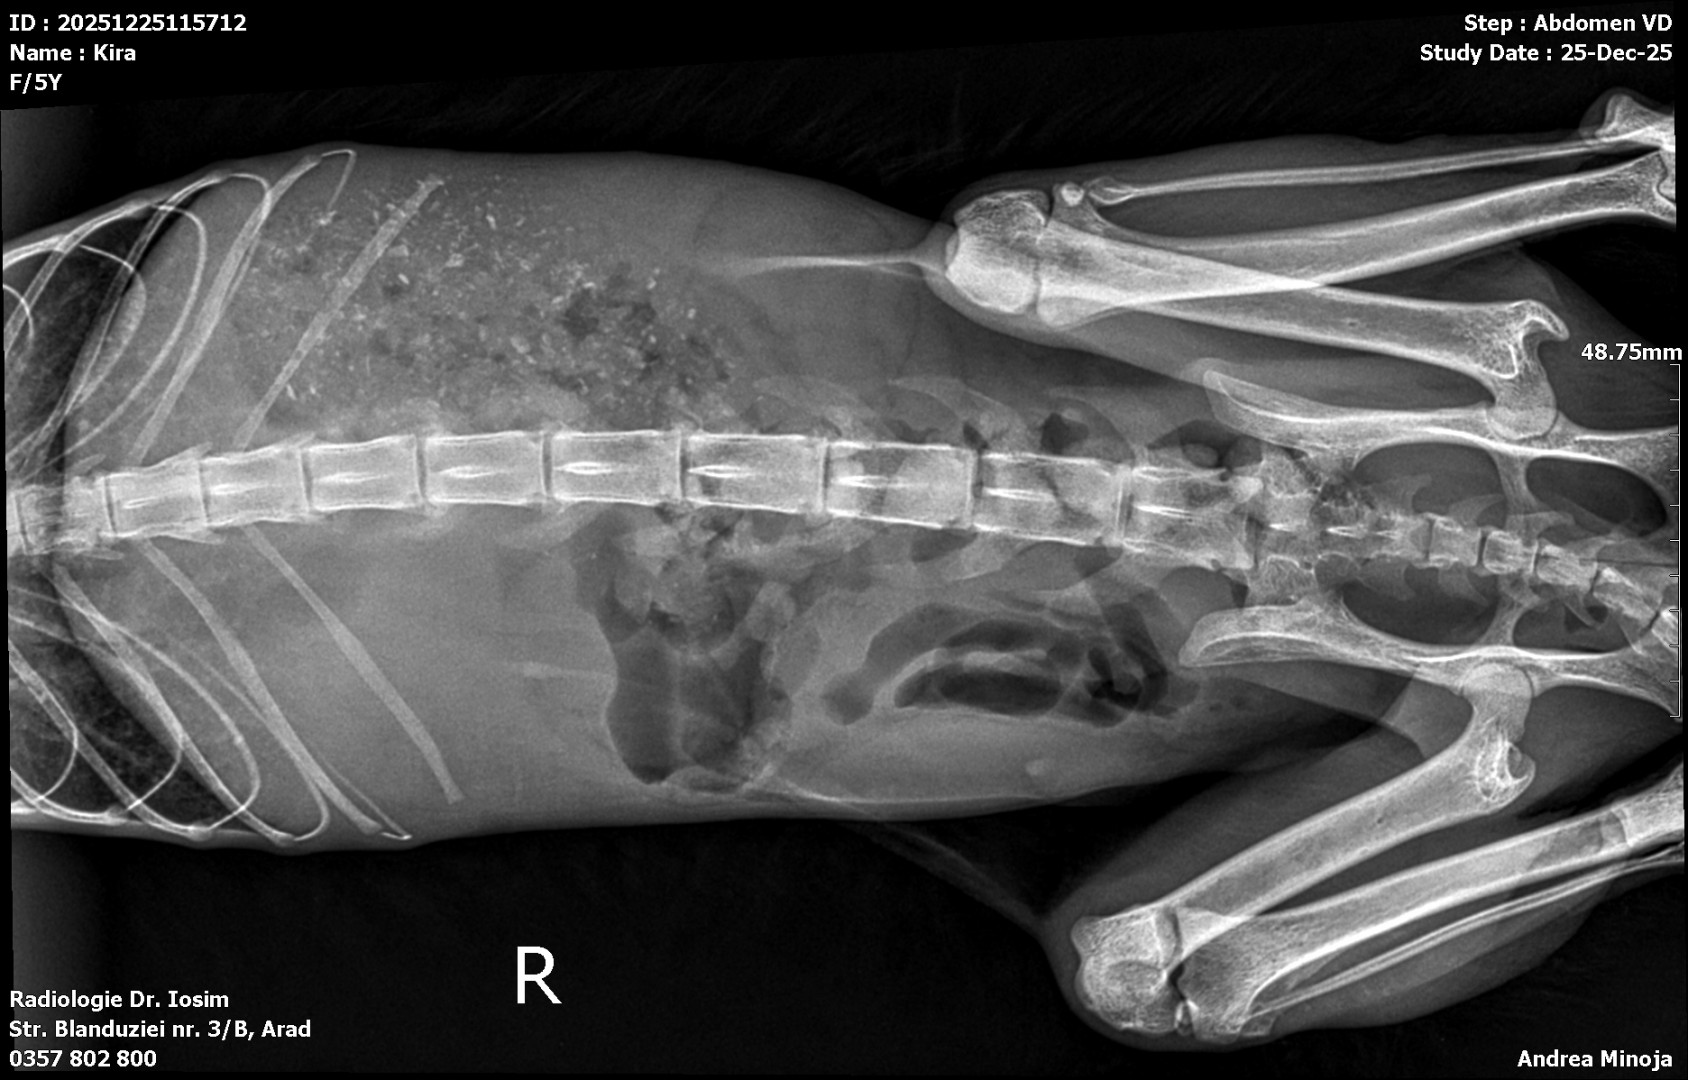

Pisica cu pancreatita

Urgenta de craciun este o pisica cu pancreatita. Am facut analize de sange si radiografii. Acum o perfuzam.